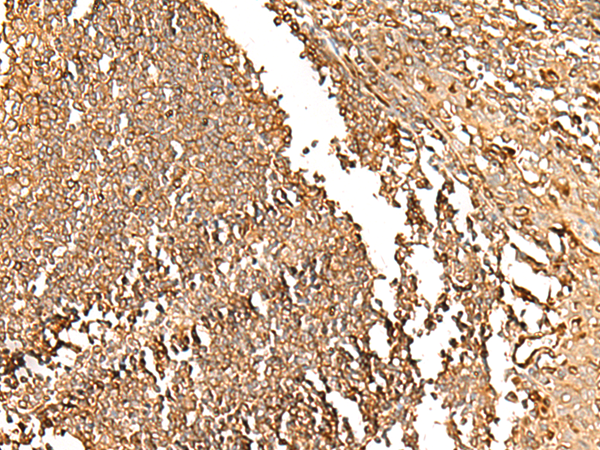

ELISA, IHC |

IHC positive control: |

Human tonsil |

IHC Recommend dilution: |

30-150 |